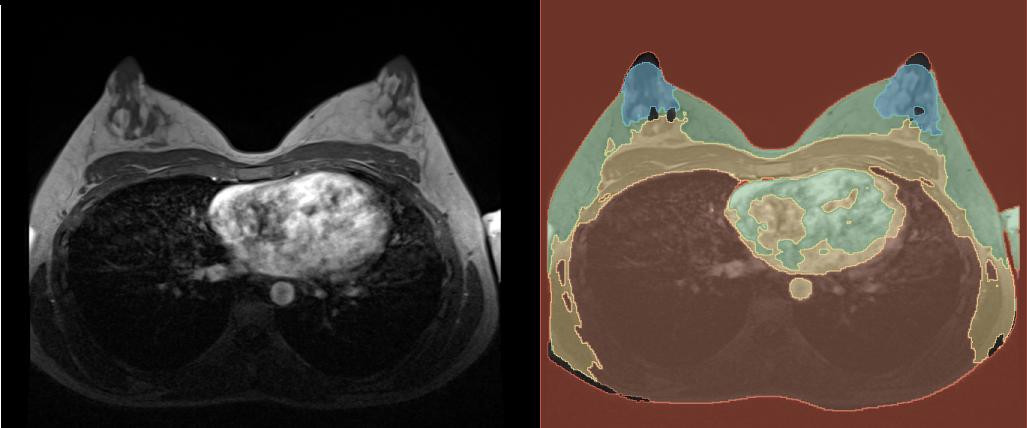

After the prediction is done, you can find the predicted segmentation in the chosen output folder. You can open it in 3D Slicer along with the reference volume to see how it turned out. In the following graphic you can see our example. You probably get a better result, if you train the model with more images and for more epochs, but also the time, the training takes, will be longer.